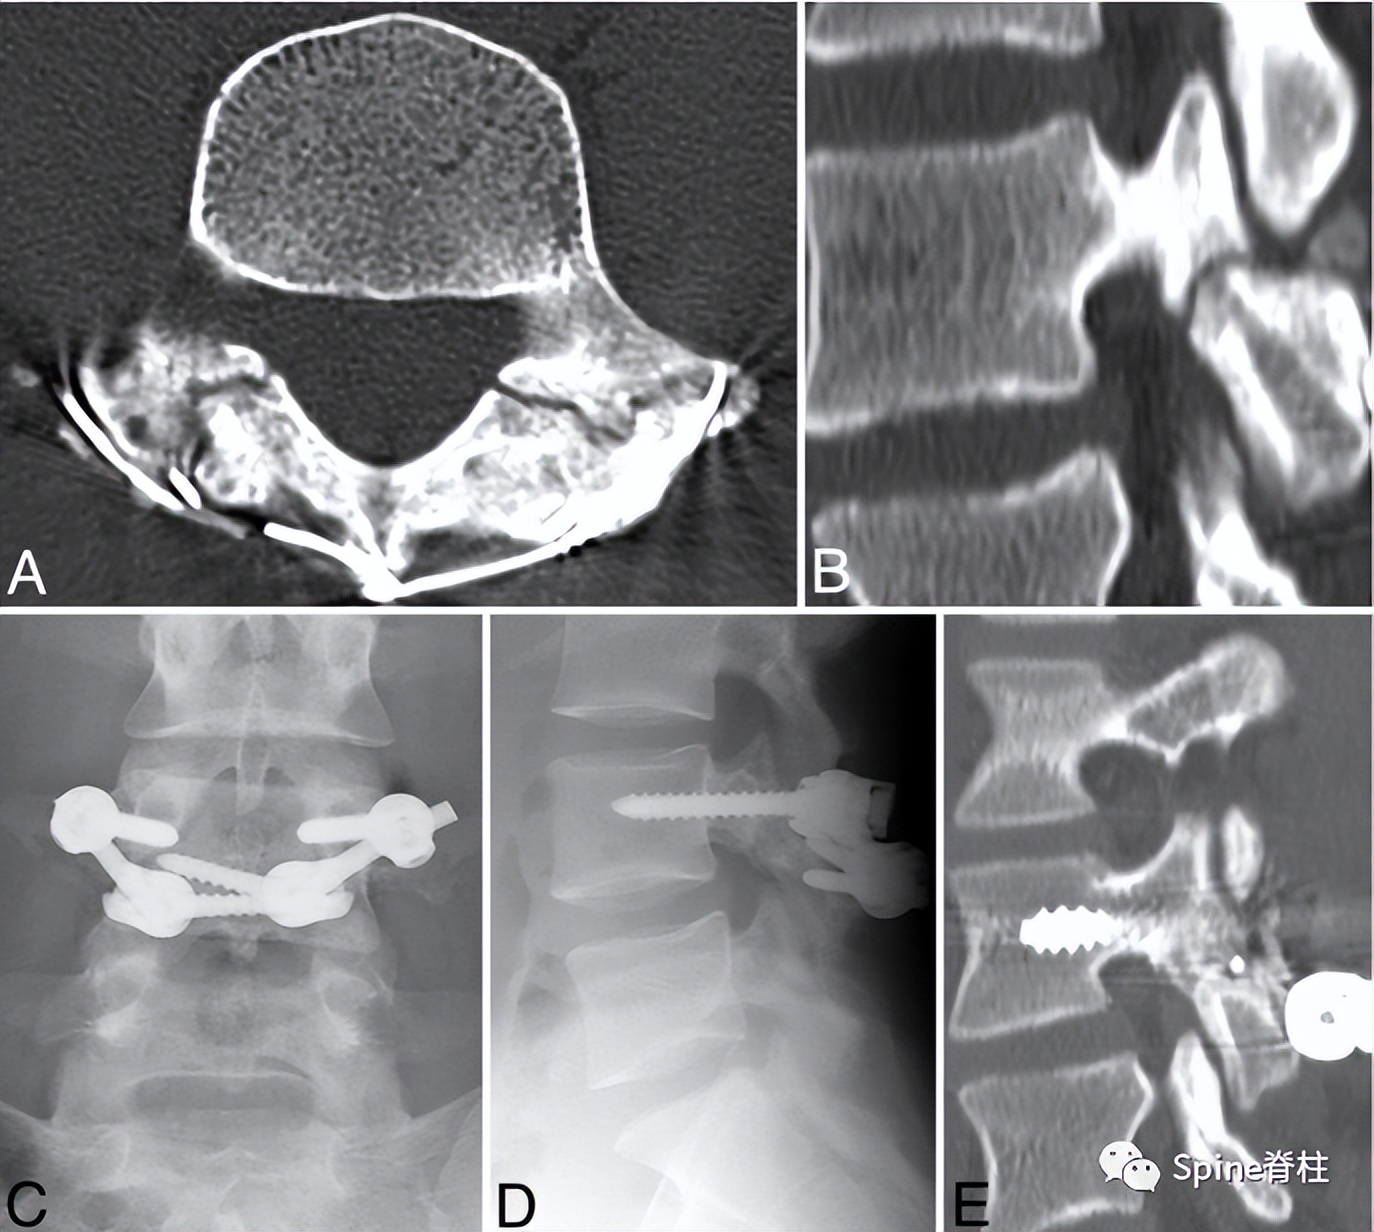

7. 解剖型钉钩椎弓根螺钉系统

2022年,解放军总医院第三医学中心彭宝淦(我的硕导和博士后合作导师)和李端明主任提出了一种新型解剖型钉钩椎弓根螺钉系统。根据腰椎解剖,棘突与椎板成一定角度,椎板向后向上倾斜,椎板下缘和椎弓根螺钉尾部与矢状面成一定角度。根据上述解剖特征,解剖型钉钩椎弓根螺钉系统的钩和棒在这三个方向上都是倾斜的。钩棒与椎板完全匹配,有利于将钉钩安装在椎板的下缘,且易于将棒与万能椎弓根螺钉连接。此外,该系统可通过肌间隙入路置入。

PMID: 35979102